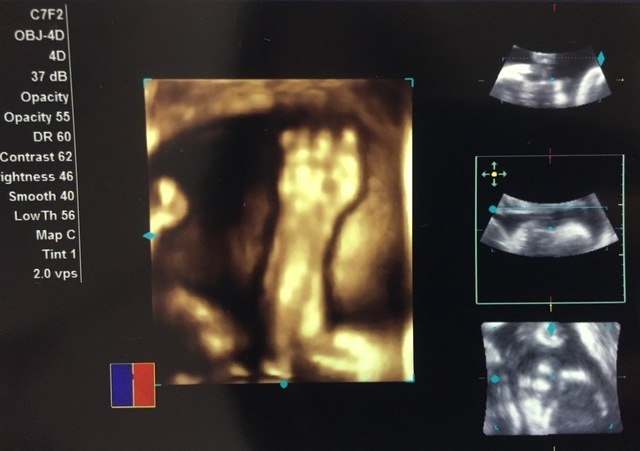

32週5日(32w5d・男の子)|おしげ さん(23歳)

エコー写真撮影時のエピソード:

妊娠9ヶ月の頃の写真です。福岡にいた私が出産のため大分に着て初めての診察で、4Dエコーするのも初めてでした。 立体的にうつる我が子をみてニヤニヤが止まりませんでした。

旦那もリアルなお腹の中の映像に感動!我が子はほっぺに手をあて、口をムニュムニュしてました。かわいいかったです。元気に生まれてきてくれた今は幸せいっぱいです。